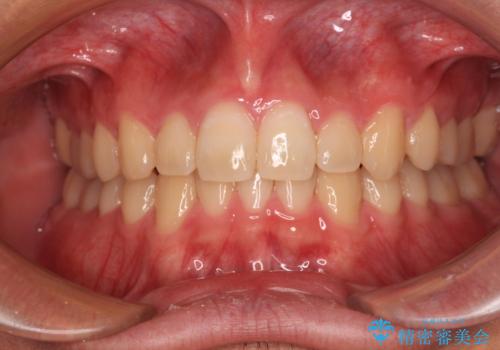

カリエール・ディスタライザーを併用したインビザライン矯正治療

カリエール・ディスタライザーを用いたことで上顎前歯の突出感はスムーズに解消され、歯列不正は1年半ほどでほぼ改善することができました。

しかし、その後インビザライン特有の奥歯がうまく噛めないという問題が長引き、改善に1年近い期間を要することとなりました。